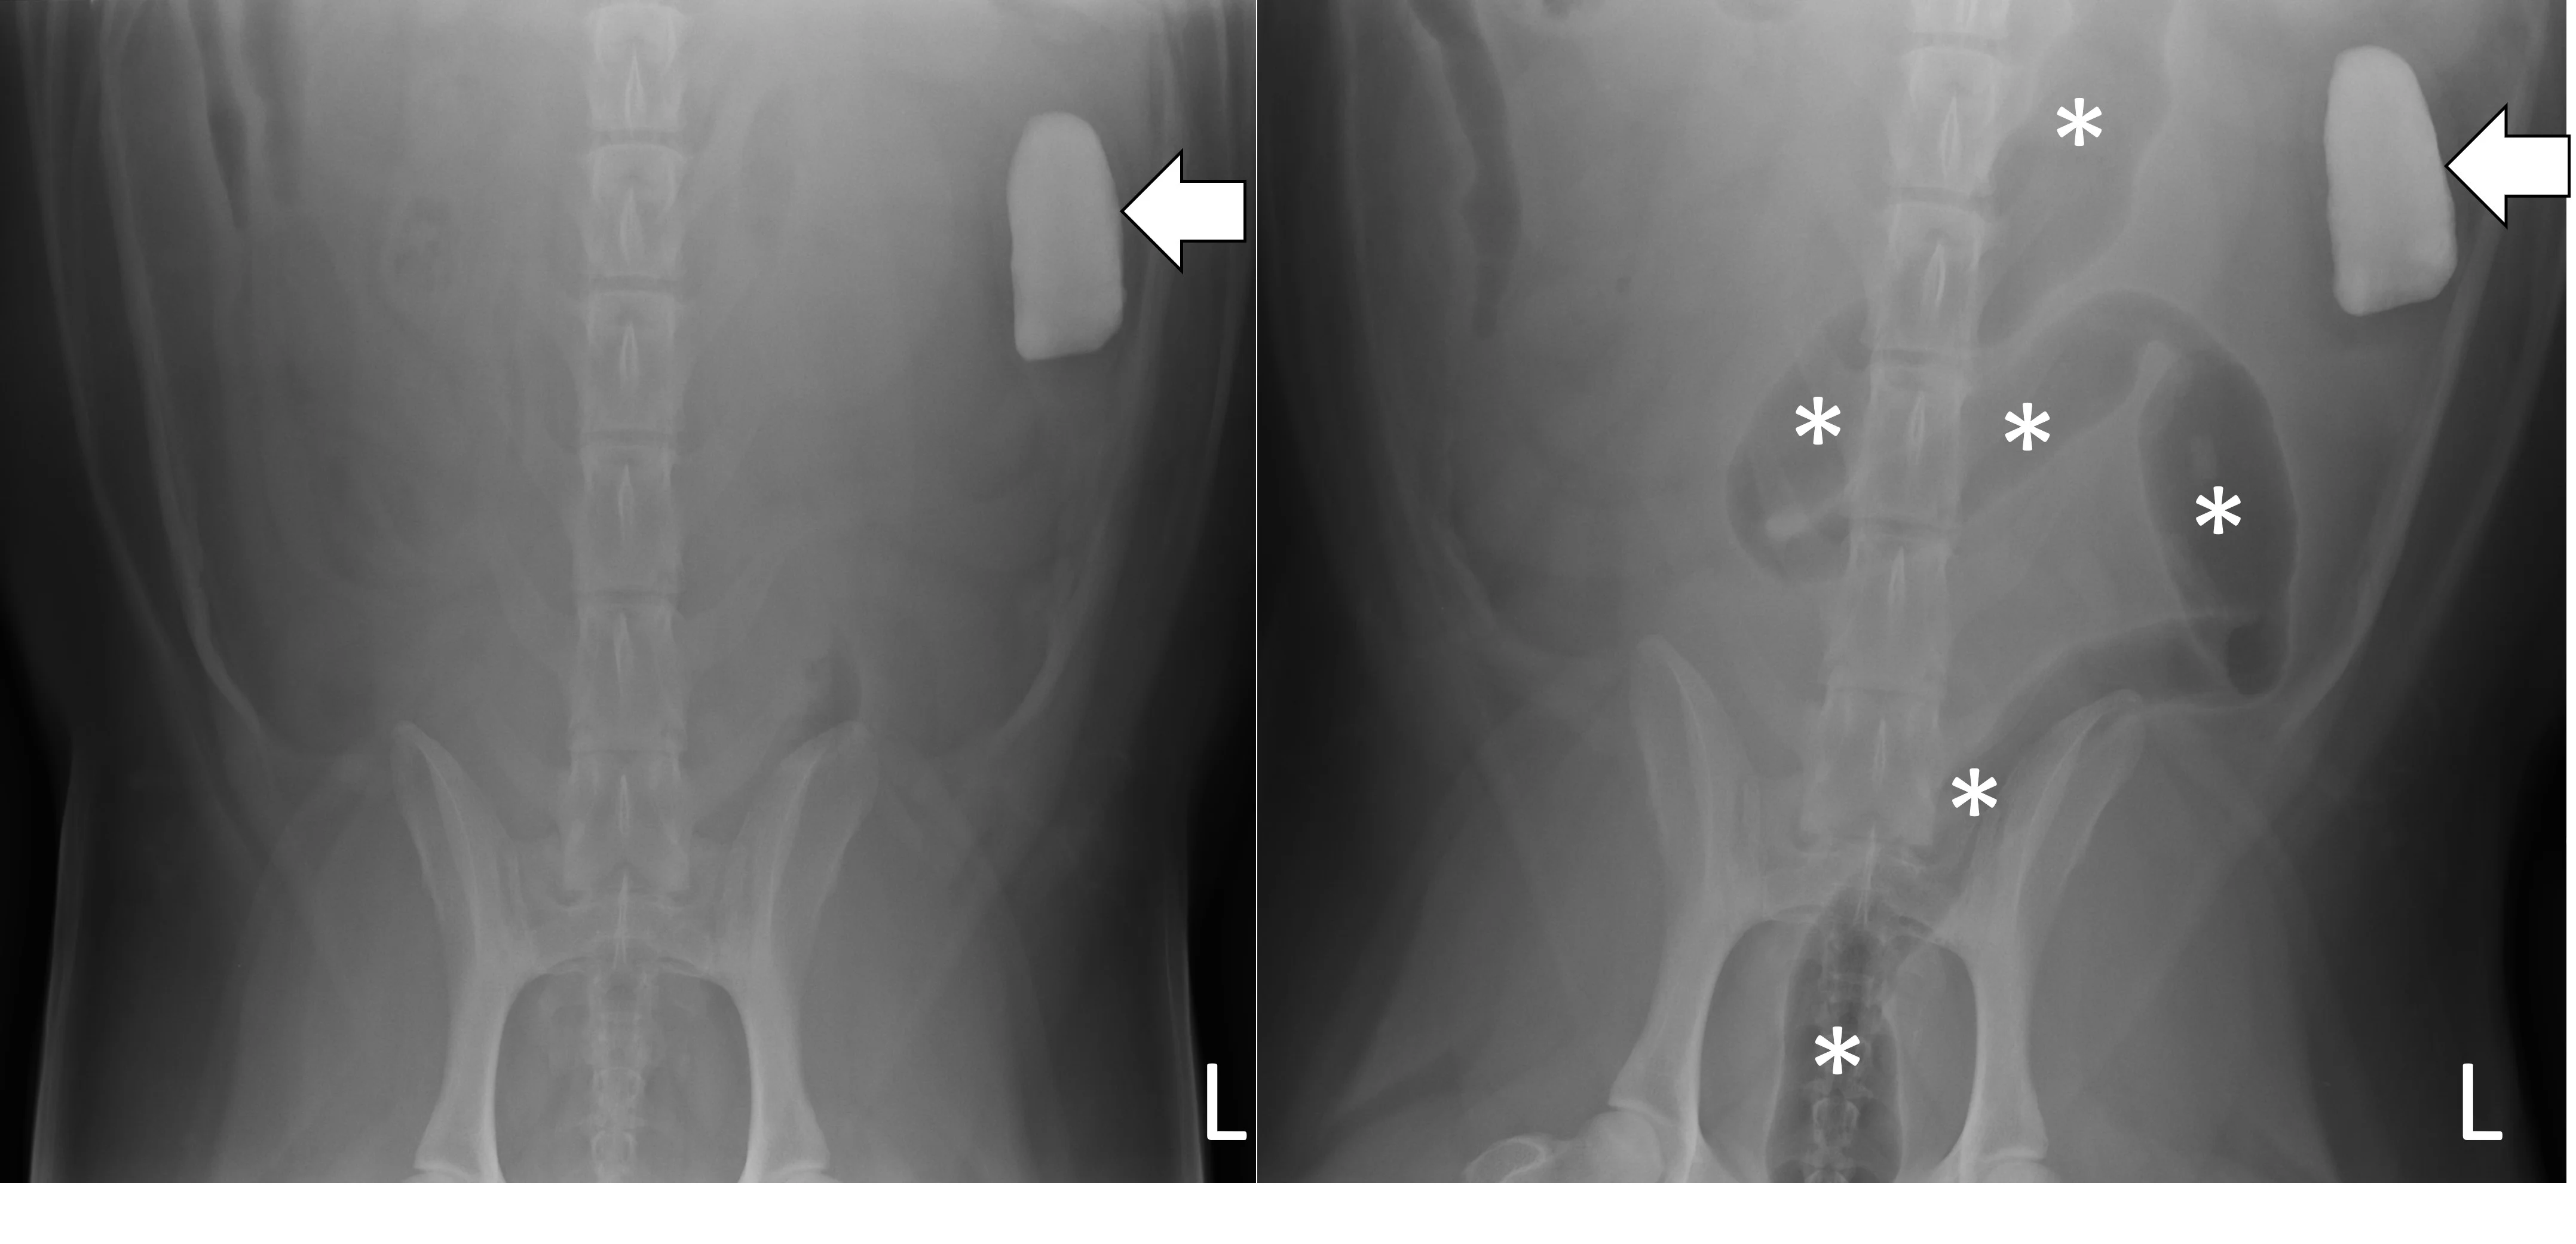

Pneumocolonogram

A pneumocolonogram can be performed to determine whether a foreign body is located in the colon or whether a focally dilated loop of intestine is part of the small bowel or colon (Figure 7).11 Sedation is often not necessary but can be used in uncooperative patients. Room air (3 mL/kg) should be administered into the rectum with an appropriately sized and lubricated red rubber catheter and syringe. Right lateral and ventrodorsal projections should be obtained immediately. The goal is to mildly dilate the entirety of the colon to the cecum with gas without overfilling the small intestine. The dose of air may need to be repeated to effect in some patients if there is inadequate filling of the entire colon.

Ventrodorsal radiographs of a 3-year-old spayed golden retriever with a small intestinal obstruction secondary to rock ingestion. Survey radiographs revealed the rock was in the left lateral abdomen but could not help determine whether the rock was in the small bowel or the descending colon (left, arrow). Pneumocolonogram was performed to mildly dilate the colon with gas (asterisks), confirming the rock was in the small bowel (right, arrow).